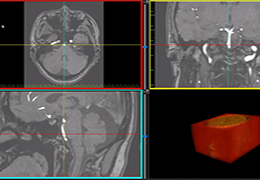

ART-Plan™ Artificial Intelligence Contouring